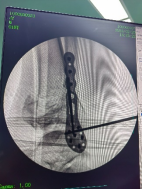

外側(cè)切口放置鋼板,固定腓骨。

穿針輔助復位脛骨遠端骨折塊,安裝內(nèi)固定